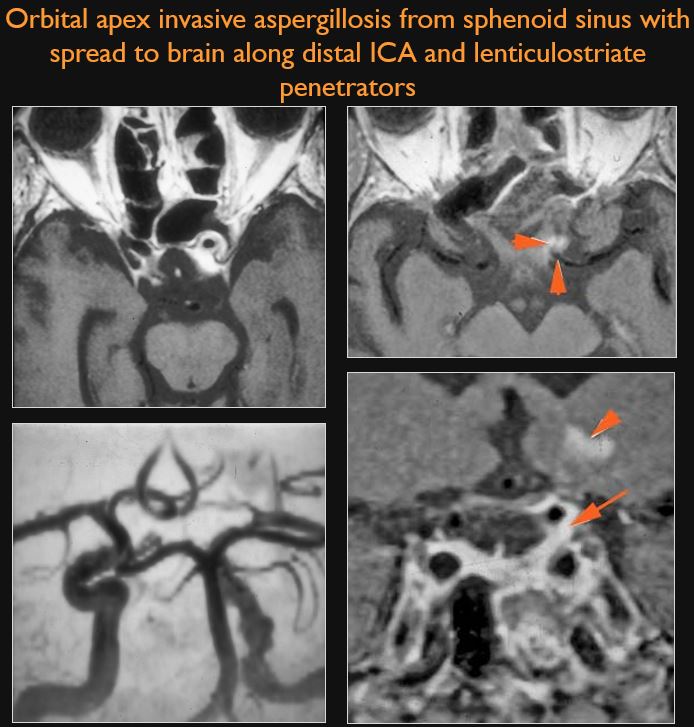

There is primary sinonasal, bone or skull base rather than a primary orbital disease process that might be causative and producing the patient’s signs and/or symptoms related to the orbit.

The bones and bony margins of the orbit including all component parts of the sphenoid bone are abnormal.

There is a structural abnormality or infiltrating process of the extraconal or intraconal compartments of the orbit.

The orbital apex and superior orbital fissure are infiltrated, edematous or otherwise abnormal.

There is evidence of cavernous sinus thrombosis and/or inflammatory morphologic features in the cavernous sinus or para-cavernous region.

There is a compressive lesion or infiltrative process present in the cavernous sinus or para-cavernous area.

There are intra-axial or extra-axial abnormalities of the brain that might be related to the orbital pathology.